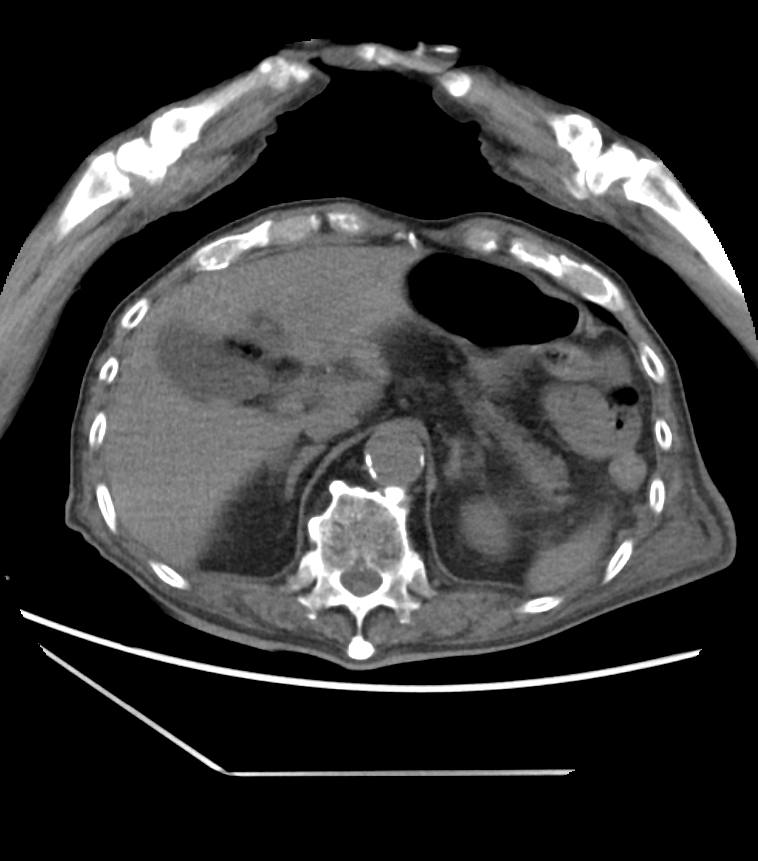

発熱 会陰部痛で来院した90歳代男性 実践 画像診断q A 羊土社 レジデントノート 羊土社